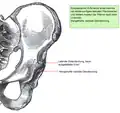

Anatomie des gesunden Beckens (Ansicht von vorne) -

Das Becken ist der Mittelpunkt des menschlichen Körpers und vereinigt die Wirbelsäule mit der unteren Extremität (Bein). Gleichzeitig liegen wichtige Organe, wie z. B. die Harnblase, der Enddarm, die Geschlechtsorgane und deren Anhänge, direkt im Beckengewölbe. Große Gefäße und Nerven (Ischiasnerv, Beckenarterie und -vene) gabeln sich hier. Schließlich setzen zahlreiche Muskeln, Sehnen und Bänder am Becken an, die für die Körperstatik und besonders für die komplexen Hüftbewegungen wichtig sind.

Die gewölbeartige Struktur des Beckens und die empfindlichen Weichteilverhältnisse (Nerven, Gefäße, Muskel-Sehnenansätze) machen die Zugangswege kompliziert.